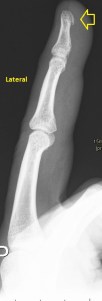

Paciente que acude derivado del traumatólogo por una sospecha rotura del extensor del pulgar. Cuando posicioné al paciente para iniciar la exploración y le hice el interrogatorio habitual, me contó que desde un traumatismo donde se rompió las dos muñecas, tiene una incapacidad para estirar completamente el dedo pulgar a la altura de la interfalángica, no de la metacarpofalángica.

1

Exploré el primer compartimento sin ningún tipo de novedad, tanto el Abductor Largo del Pulgar y Extensor Corto del Pulgar. Pasé al compartimento dos, Extensor Radial Largo del Carpo y Extensor Radial Corto del Carpo, ellos dos estaban sin novedad, pero este compartimento guarda una particularidad y una relación especial con el tercero, que es el del Extensor Largo del Pulgardel que está separado por tubérculo de lister, esta relación consiste en la coexistencia de los tres extensores y del paso superior o superficial que el extensor largo del pulgar realiza en un punto sobre el compartimento 2. Es importante que entiendas anatómicamente esta relación y te la enlazo aquí.

Lo que hace el tercer compartimento nada más desplazarnos hacia distal en el corte axial de la muñeca en su cara extensora y donde visualizamos el tubérculo distal separando ambos compartimentos 2 y 3, lo que hace el tercer compartimento, decía, es cruzarse por encima del dos para buscar diagonalmente su paso y su inserción en la cara dorsal del dedo pulgar. Si no entiendes esta anatomía, no vas a poder entender lo que pasa.

Lo que me llamó la atención fue que la parte superficial del segundo compartimento, correspondiente con el extensor largo del pulgar cruzando por encima del compartimento 2, era que estaba muy hipoecogénica y grande, así que una vez comprobado que los dos tendones del compartimento eran normales, y sabiendo que el tercero pasa por encima para cruzarse buscando el primer dedo, lo que hice fue seguir el tercer compartimento y lo que ví era que estaba situado en su lugar junto al tubérculo de lister, proximalmente, que a su cruce por encima del compartimento dos, estaba hipoecogénico y gordo y que ya en la mano, por donde cruza buscando el primer dedo, no estaba o al menos no estaba íntegro.

En este recorrido encontré un muñón, que se observa perfectamente en longitudinal, y que correspondía con el extensor largo del pulgar a la altura de su recorrido.

2

El extensor es claramente visible y palpable, te lo indico, pero tu misma puedes objetivarlo si te observas tu mano y realizas una extensión forzada del primer dedo. Con toda esta descripción, que espero que te haya quedado clara, situando la zona donde el tendón estaba roto (punto rojo), te dejo las imágenes que son muy esclarecedoras, con su anatomía ecográfica para que identifiques cada paso que dí en esta exploración, siempre en función y en estrecha relación con el conocimiento de la anatomía en ese lugar.

3

En esta imagen quiero que te fijes en el segundo compartimento y como el extensor largo del pulgar pasa por encima, los dos tendones del compartimento dos cortados en eje corto y el del tercero, cortado, pero en un corte para-axial. Lo importante es que te fijes en la ecogenicidad de ELP, en la izquierda hiperecogénico, isoecogénico con el segundo compartimento, por tanto normal. En la derecha hipoecogénico y más gordo, patológico.

4

Seguimos avanzando hacia distal, seguimos observando las mismas diferencias en las imágenes comparativas. Imagen justo antes de la rotura.

5

En la rotura el tendón es muy pequeño, pero normal en la izquierda y en la derecha lo es igual de pequeño, pero aplanado y con la pérdida de la ecogenicidad normal.

6

Después de la rotura, avanzando a distal, el tendón retraído, hipoecogénico, mucho más grande que su comparativo contralateral.

7

Corte en eje largo correspondiente a la imagen 6, donde se ve claramente lo que pasa y es definitivo para el diagnóstico final.

8

Comprobar con doppler para ver si hay actividad, que no la hay y es que la lesión no es reciente y esto podría explicar tal circunstancia.

En resumen, desde la imagen 3 a la 8 observas el recorrido ecográfico del tendón extensor del pulgar desde proximal hasta distal, pasando por el foco de rotura y terminando con el muñón en axial y en longitudinal según marcan los pictogramas.

La imposibilidad de poder extender el pulgar quedaba explicada con estos hallazgos. Un caso muy bonito, que espero que te sirva, sobre todo para que veas lo importante de la anatomía en esta técnica de la MSK.

9

Esta imagen final demuestra muy claramente lo que ha pasado y como ha quedado la zona en cuestión. El tendón retraído parece continuarse hacia proximal, filiforme, hasta que llega a otro ensanchamiento hipoecogénico, en relación con el muñón proximal.